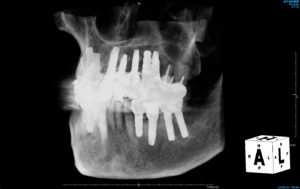

埋入ポジションや埋入深度などがそれぞれ異なりますので、CTで見ると何となく不揃いですが、24年経過するアストラテックインプラントをはじめとして、現在すべて良い状態です。